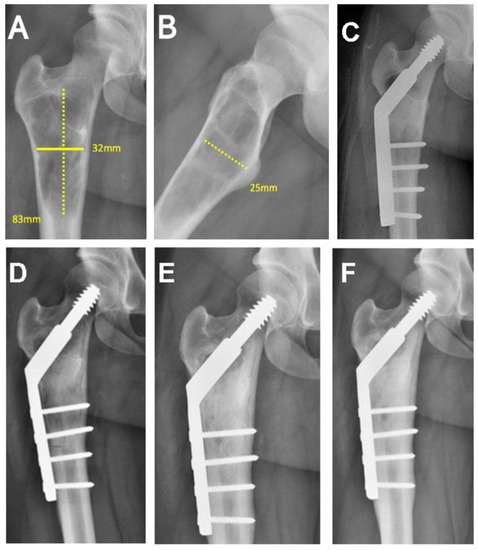

| 19/F/15 | Proximal femur | Simple bone cyst | 52.25 |